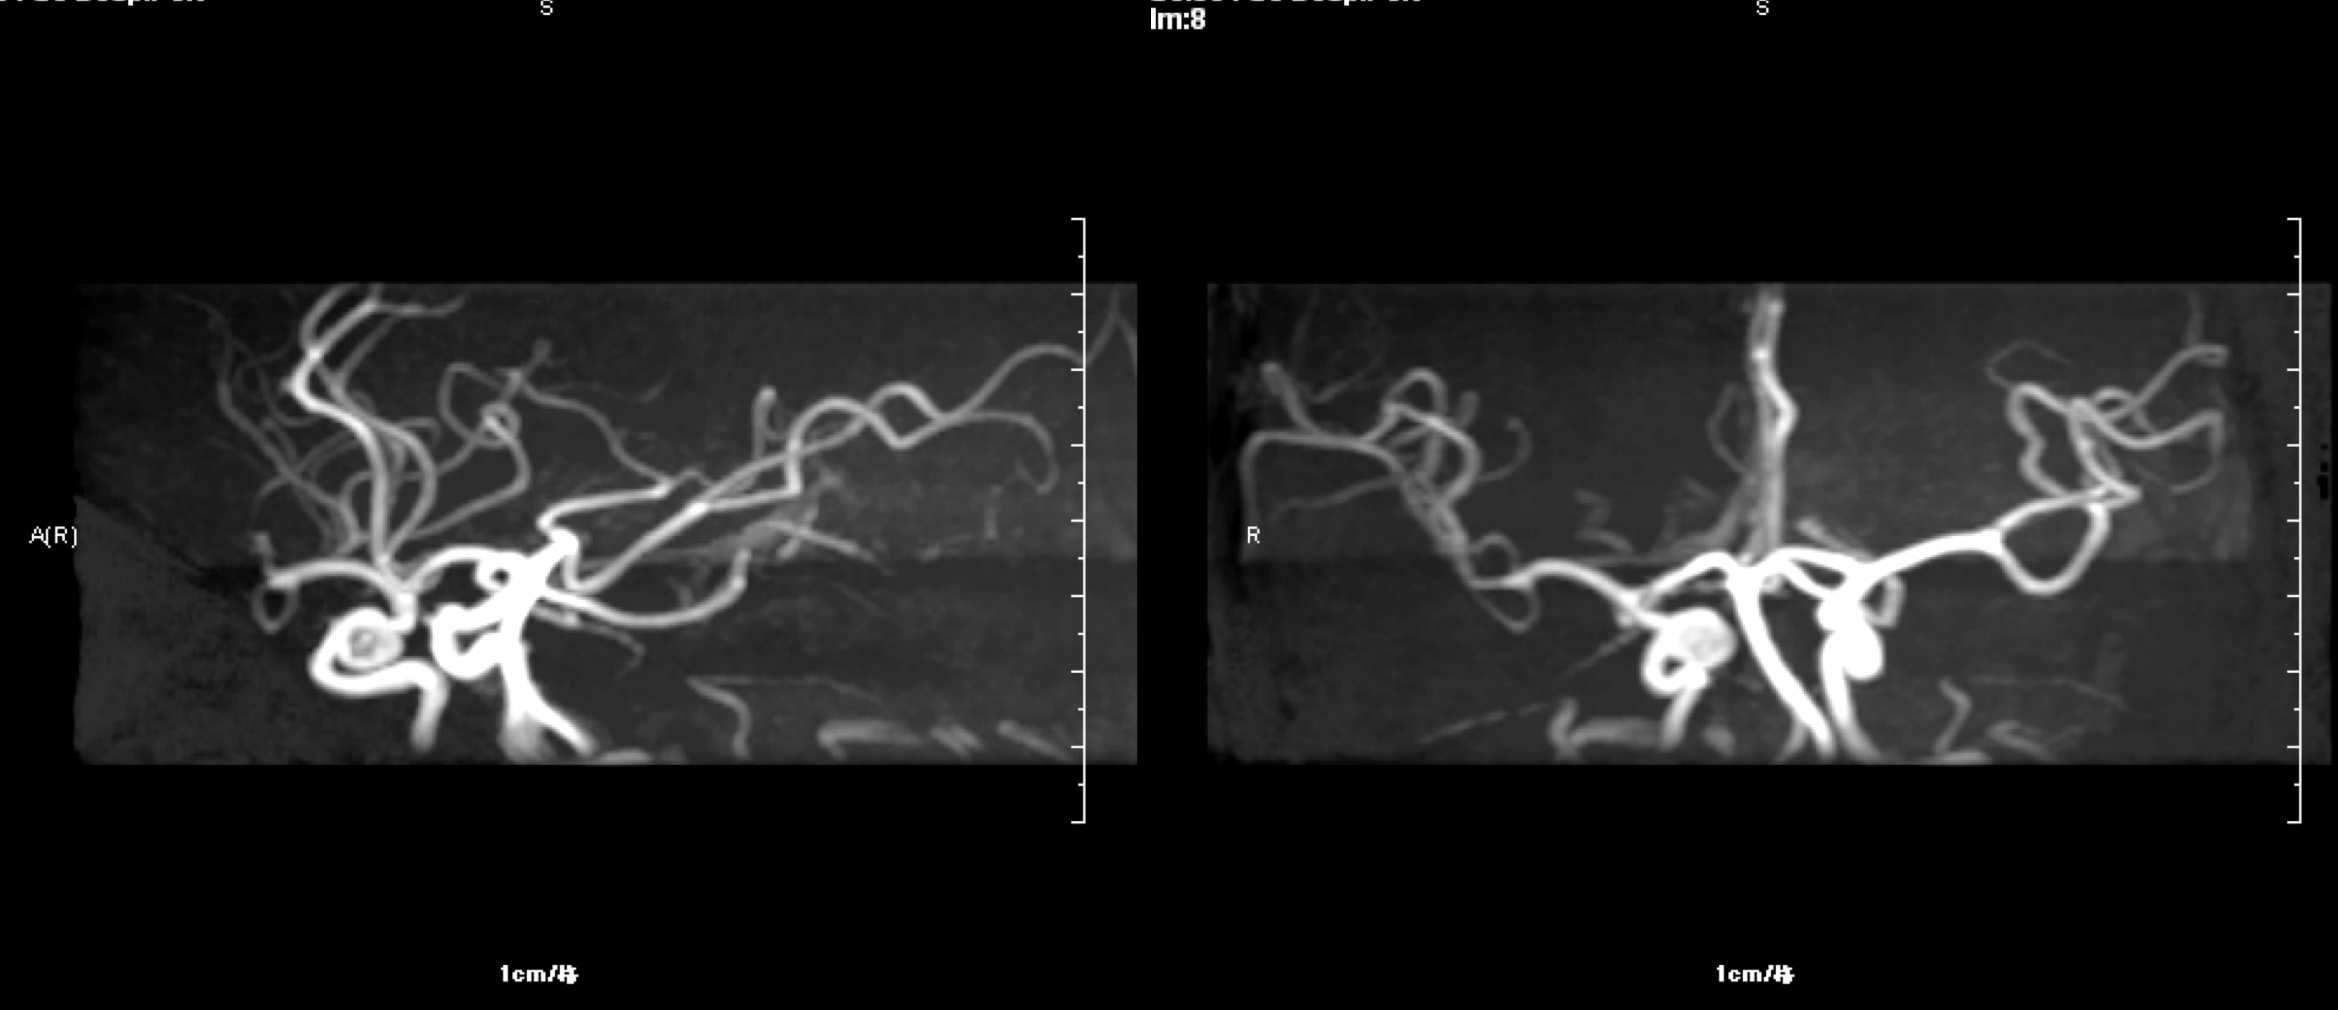

入院头颅MRA:右侧眼动脉段动脉瘤.